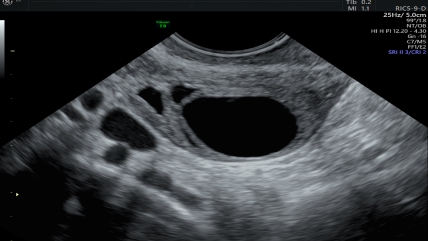

Ovarian cysts are fluid-filled sacs or pockets in your ovary or on its surface. These are common and, most of the time, painless and harmless. You might get one once a month along with your menstrual cycle. These usually go away on their own. The cyst becomes a problem when they do not go away and start to grow bigger.

Ovarian cysts are generally small and don't cause any problems. Though there's a possibility of cancer, it can be rare. As you get older, the chances also go up. Hormone problems, endometriosis, a severe pelvic infection, or a previous cyst can lead to an ovarian cyst.